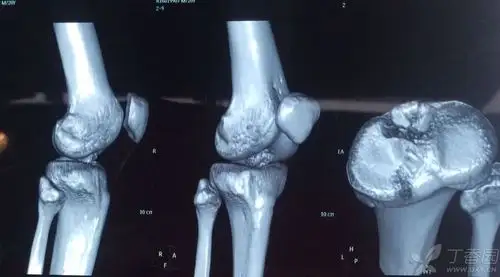

胫骨髁间棘骨折

关节镜下单骨道单对纽扣钢板固定治疗大块胫骨髁间嵴骨折